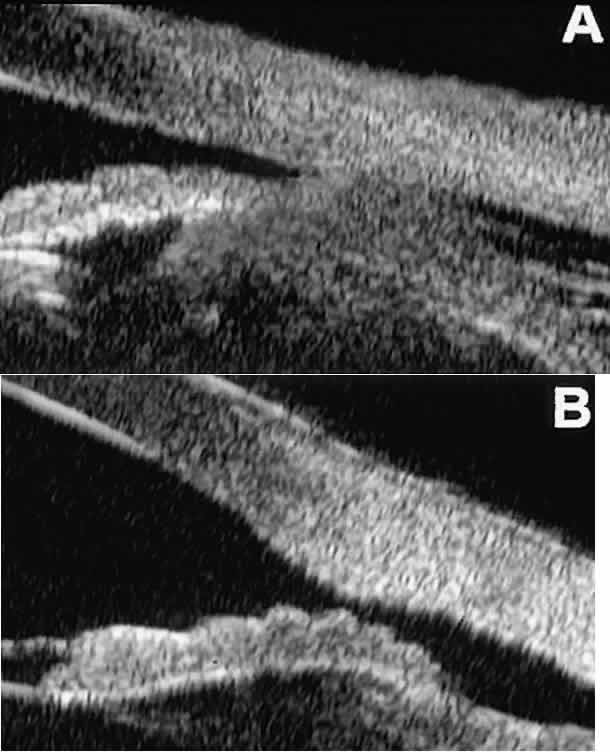

Postoperative UBM imaging of the anatomic changes caused by glaucoma surgery often helps to explain mechanisms of success and failure of the various surgical procedures (Fig. 12).3,4 After laser iridotomy, UBM can show whether the iridotomy is partial thickness (see Fig. 12A) or full thickness (see Fig. 12B) and whether the plane of curvature of the peripheral iris has changed compared with the pretreatment findings. After trabeculectomy (see Fig. 12C), UBM can show whether the scleral aperture is patent or blocked internally, whether the peripheral iridectomy is open or blocked, and whether the filtering bleb is flat, shallow, or deep.9 After tube shunt surgery (see Fig. 12D), UBM can show the position of the tip of the tube and whether its orifice is open or plugged.

Fig. 12. UBM features in glaucomatous eyes after treatment or filtering surgery. A. Incomplete peripheral iridectomy created by laser. B. Full-thickness peripheral iridectomy created by laser. C. Postoperative features of trabeculectomy including peripheral iridectomy, inner scleral defect, thin residual scleral flap, and overlying conjunctival filtering bleb. D. Tube shunt projecting radially into anterior chamber; note that the tube “shadows” deeper structures.

After any type of glaucoma filtering surgery,10 UBM can be used to detect and evaluate the extent of postoperative complications such as ciliochoroidal effusion and cyclodialysis.3,4 In ciliochoroidal effusion (Fig. 13A), UBM shows the ciliary body to be edematous and separated from the sclera by a sonolucent collection of supraciliary fluid. Many ciliochoroidal effusions that are too limited in extent to be detectable by indirect ophthalmoscopy and slit lamp biomicroscopy can be imaged by UBM. In cyclodialysis (see Fig. 13B), UBM shows a well-defined separation between the uveal tissue and the sclera in the region of the scleral spur. The width of the cleft is usually assessed best by means of limbus-concentric images through the region of interest.

Fig. 13. Complications of intraocular surgery. A. Postoperative ciliochoroidal effusion appears as slitlike spaces filled with serous fluid posterior to scleral spur. B. Postoperative cyclodialysis appears as complete separation of iris and ciliary body from sclera in region of scleral spur.